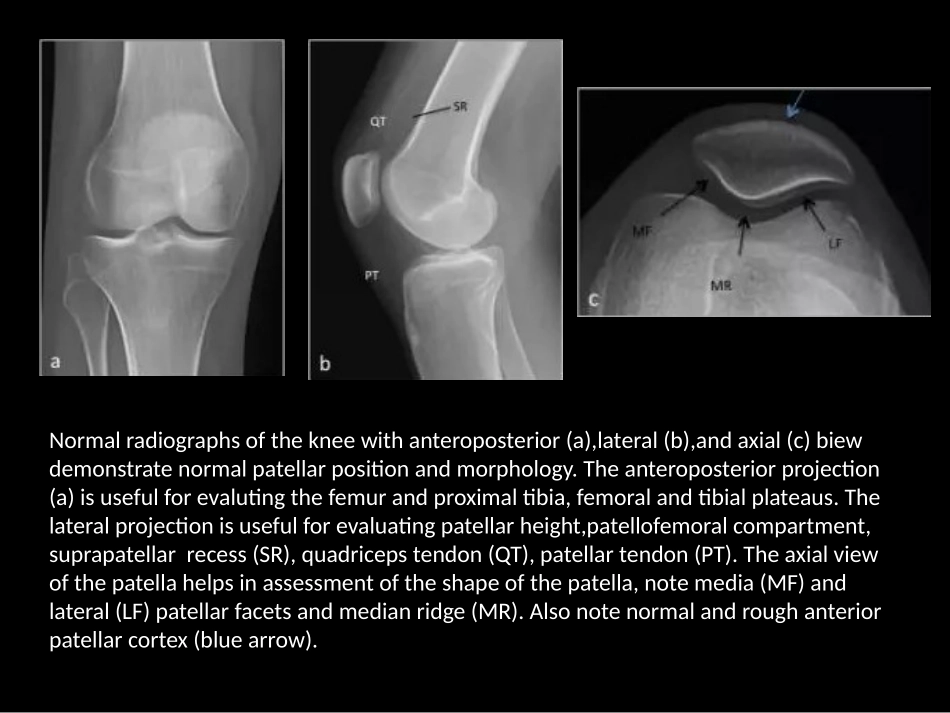

Normalradiographsofthekneewithanteroposterior(a),lateral(b),andaxial(c)biewdemonstratenormalpatellarpositionandmorphology.Theanteroposteriorprojection(a)isusefulforevalutingthefemurandproximaltibia,femoralandtibialplateaus.Thelateralprojectionisusefulforevaluatingpatellarheight,patellofemoralcompartment,suprapatellarrecess(SR),quadricepstendon(QT),patellartendon(PT).Theaxialviewofthepatellahelpsinassessmentoftheshapeofthepatella,notemedia(MF)andlateral(LF)patellarfacetsandmedianridge(MR).Alsonotenormalandroughanteriorpatellarcortex(bluearrow).Sagittalprotondensity(a)andaxialfat-suppressedT2-weighted(b)MRimagesofanormalknee.Notethelowsignalpatellar(PT)andquadriceps(QT)tendonsandthethick,homogeneous-appearingpatellarcartillage(redarrows).Notethelateralandmediaretinacula,passivestabilizersofthepatella.In1941,Wibergclassifiedpatellarshapeintothreedifferentmorphologies:TypeI(a)demonstratesroughlysymmetricandequal-sized,concavemedial(MF)andlateral(LF)patellarfacets.TypeII(b)showsamedialfacetthatisslightlysmallerthanthelateralfacetandaconcavelateralfacet.TypeIII(c)alsoshowsasmallerandmoreverticallyorientedmedialpatellarfacet,whichisassociatedwithmaltrackingdisorders[18].5-year-oldmalewithhereditaryosteo-onychodysplasia(nail-patellasyndrome).AP(a),later(b),andaxial(c)viewsofthekneedemonstratecompleteabsenceofthebilateralpatellarossificationcenters.Anteroposteriorandaxialradiographs(a)showbilateral,well-corticatedossifiedfragmentsinthesuperolateralaspectofthepatellas(arrows).CoronalandaxialT2-weightedfat-suppressedMRimage(b)showthewell-corticatedossifiedfragment.Notethenormalbonemarrowsignalandcartilageacrossthesynchondrisis,Thewell-corticatednatureofthefragmentandlackofabnormalmarrowsignalhelptodifferentiatethisentityfromapatellarfracture.Anteroposterior,lateral,andaxialradiographs(s)showalucent,roundlesionwithwell-definedmarginsatthesuperolateralaspectofthepatella(arrows).SagittalprotondensityandaxialT2-weightedfat-suppressedMRimages(b)showafocalsubchondralosseousdefectwithintact-appearingoverlyingcartilage;thecartilageisthickened,andfillsthedefect.Thereisnormalbonemarrowsignalandsmooth,homogeneoussignalofthearticularcartilage.Congenitalpatellaaltaisananatomicriskfactorforpatellofemoralinstability.Theinsall-Salvatiindexistheratioofthelengthofthepatella(PL)tothepatellartendon(PT).Thenormalvalueisbetween1.0and1.2,withincreasedvaluesindicatingpatellaaltaanddecreasedvalueindicatingpatellabaja.Lateralradiograph(a)atapproximately30degreesofkneeflxionshowsanoemallyplacedpatella,withInsall-Salvatiindexof1.1.Lateralradiograph(b)ofan8-year-oldmaleshowspatellaalta,withInsall-Salvatiindexmeasuring1.8.AxialT2-weightedtubrospinechoMRimage(c)formthissamepatientshowsfindingofalateralpatellardislocation.Thereisbonemarrowedemaofthemedialaspectofthepatella(arrow)anddisruptionofthemedialpatellarretinaculum(asterisk).Thispatienthadahistoryofrecurrentdislocations,likelyduetohiscongenitalpatellaalta.Anteroposterior(a)andlateral(b)radiographsofa15-year-oldfemalepatientwithcingenitalright-sidedpatellabaja.Lateralradiographsofapatientoneyearfollowingtotalkneearthroplastydemonstratespatellabaja.Thepatellartendonisscarredtotheuppertibia(arrow).Patellabajamayalsobeseeninassociationwithneuromusculardiseases.Fromtal(c)andlateral(d)radiographsinthispatientwithahistoryofpolioshowmarkedpatellabaja.Alsonitethat...